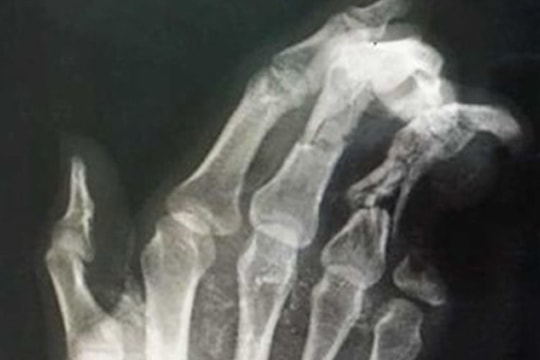

Điện thoại phát nổ khi đang sạc, bé trai 12 tuổi dập nát bàn tay

Chơi game trong lúc đang sạc pin thì chiếc điện thoại bất ngờ phát nổ khiến cả bàn tay của bé trai 12 tuổi bị dập nát